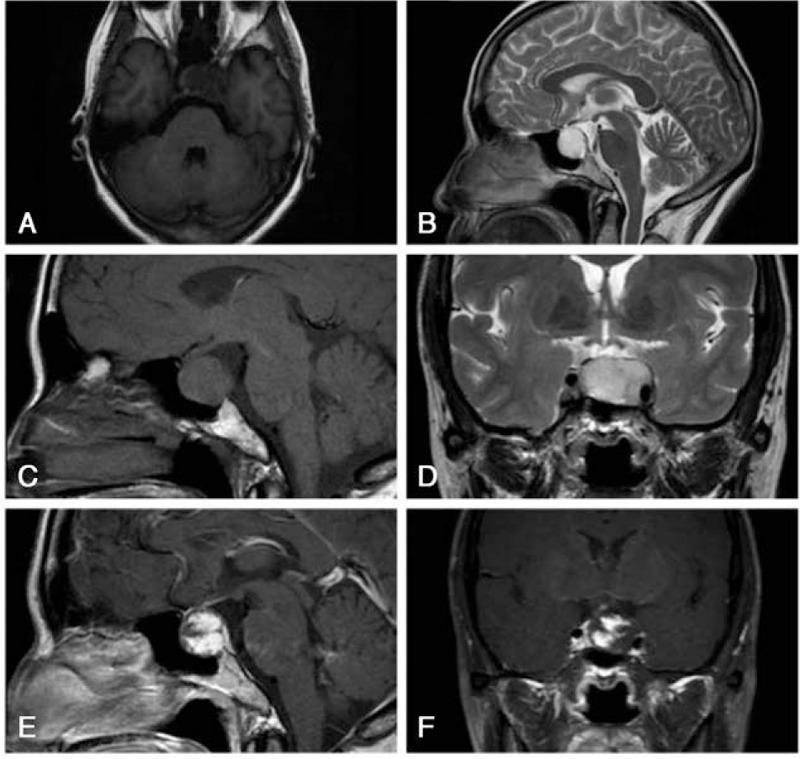

A 55-year-old woman presented with a 1-month history of intermittent dizziness. Magnetic resonance imaging (MRI) revealed a well-demarcated abnormal ellipsoid signal in the sellar region (size: 2.7 cm × 1.7 cm), with a mulberry-like enhancement after gadolinium injection. Computed tomography revealed an intrasellar mass without calcification that extended into the left cavernous sinus and was faintly contrast-enhanced. Angiography revealed a tumor with mildly delayed staining fed by the C5 segment of the right internal carotid artery.

An intrasellar cavernous hemangioma based on neuroradiological examinations.

Sponge-like or mulberry-like lesions can be identified on MRI after gadolinium injection and can facilitate a preoperative diagnosis of ICH. Currently, surgical debulking with cranial nerve decompression during the acute stage and subsequent gamma knife radiosurgery are considered to be a safe and effective treatment.